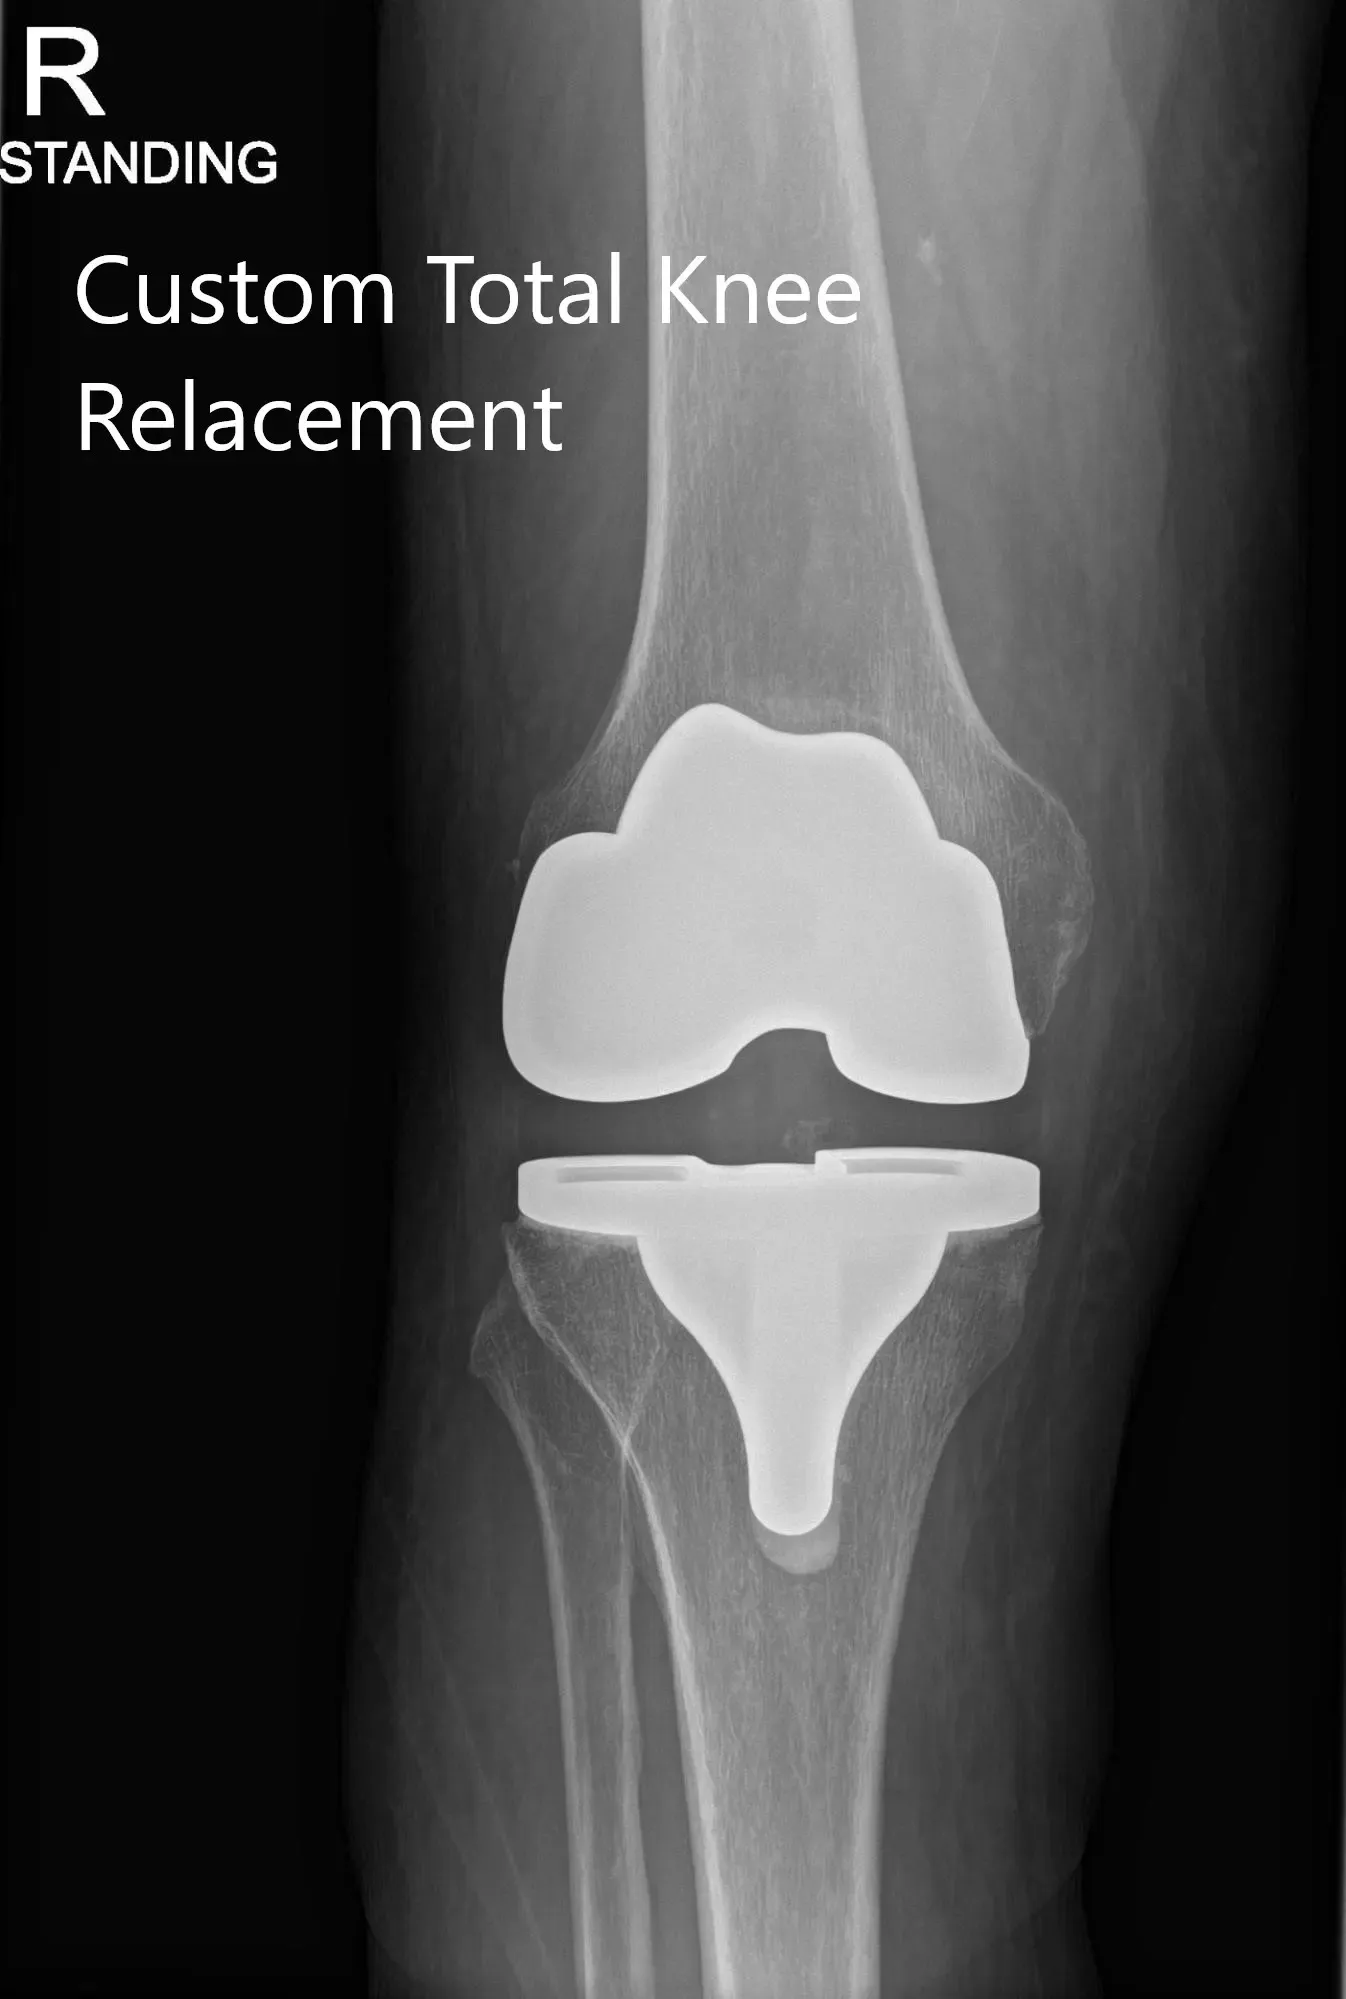

Post Operative X-ray of the patient’s right knee showing AP and Lateral Views

The patient underwent Right Total Knee arthroplasty using custom total posterior stabilized knee with 14mm posterior stabilized polyethylene implant with custom tibial tray and patellar component.